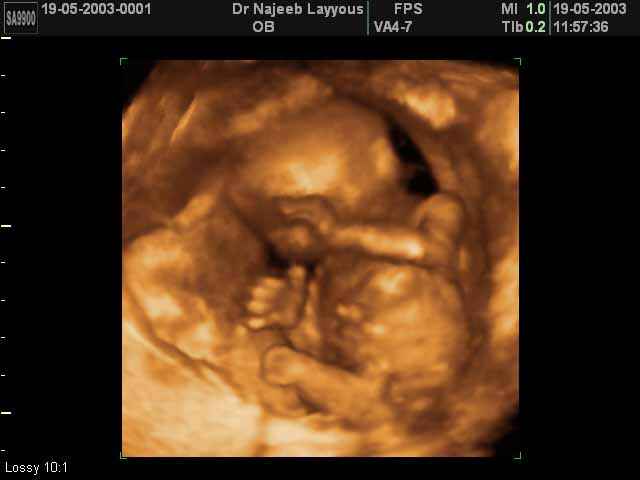

3D second trimestre échographie Photos de numérisation - deuxième partie de la grossesse | Dr N Layyous

3D second trimestre échographie Photos de numérisation - deuxième partie de la grossesse